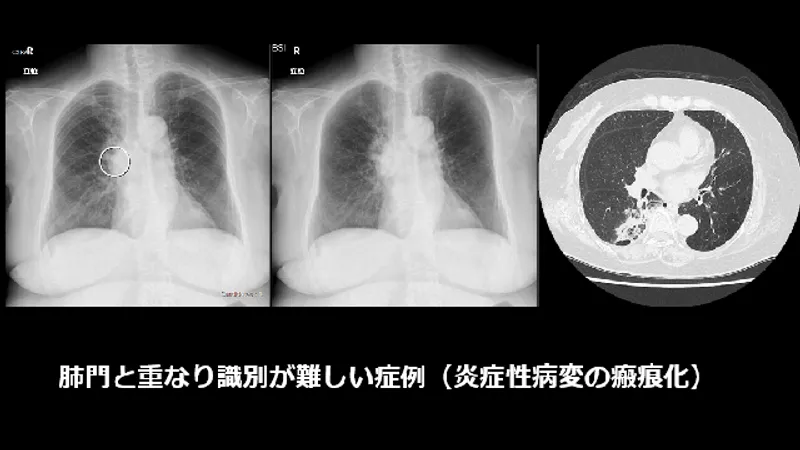

以前から提供している胸部読影支援の画像処理「Bone Suppression処理(胸部骨減弱処理)」や「Temporal Subtraction処理(胸部経時差分処理)」と併用することも可能です。 Bone Suppression処理で骨を減弱させることで、骨と重なった病変の視認性が向上し、AIと併用することによって、より読影精度の向上が期待できます。 また、Temporal Subtraction処理で現在と過去の差分画像を生成すると、経時的な変化が可視化されるので、経過観察が容易になります。

慶應義塾大学病院にて実施したCXR Finding-i読影実験の結果 AI無し読影にて見逃された病変の内、 経験の浅い医師で 67% (55/82病変)、 経験の豊富な医師で 66% (23/35病変) がAI使用により拾い上げられました。